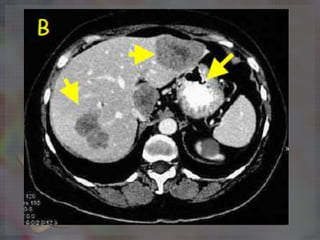

Los sitos más

frecuentes de

metástasis a

distancia son:

Hígado 54%,Pulmón

22%,Páncreas 19%,

Glándula suprarrenal

15% y Hueso 11%.

Los sitos más frecuentesde metástasis a distancia son: Hígado 54%,Pulmón 22%,Páncreas 19%, Glándula suprarrenal 15% y Hueso 11%.